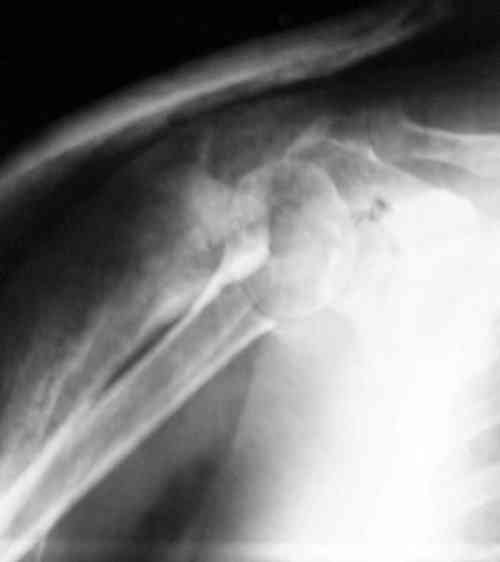

Снимки на 1-е сутки после репозиции и на 8- сутки после репозиции.

Пожалуйста

С ув. Sergey A. Melashenko, г. Запорожье

Головка плечав небольшом варусе или это проекционное?

-Головка плеча в небольшом варусе или это

проекционное?

Да, там имеем небольшой варус, надеемся, что в будущем проблемы не будет.